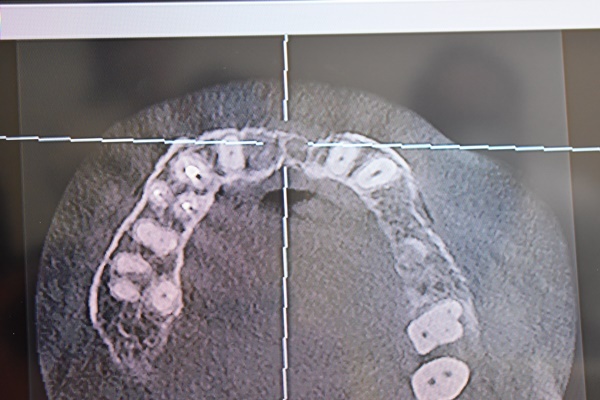

因為他在看完奶奶牙齒實際情況跟X光後,

首先指出奶奶口腔內有不少因為蛀牙而斷掉的「殘根」,

留下殘根並非不會痛,有時候是因為害怕看醫生或是有經濟上的考量,